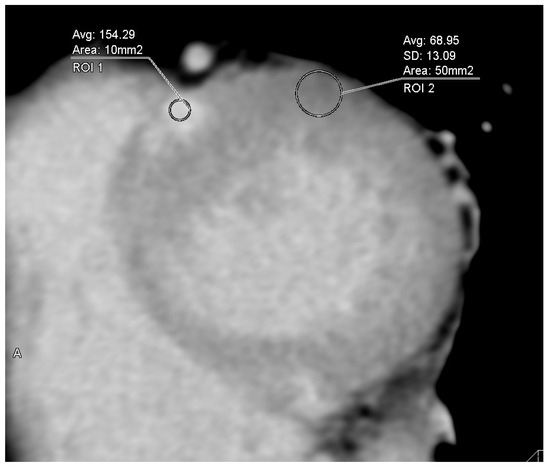

2.2. Analysis of Cardiac CT Images Including ECV